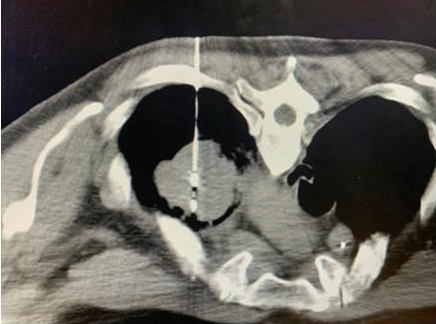

八旬胰腺癌患者肖奶奶在静脉全麻下进行了纳米刀消融术,由复大微创消融专家牛立志博士主刀,在B超加CT扫描定位下,将两支电极针穿刺至患者胰腺肿瘤内进行消融。手术一周后,患者便可出院。

湖南胰腺癌患者肖奶奶已80岁高龄,传统外科手术风险尤高,加之肿瘤侵犯到周围血管,多家医院不建议其做开腹手术。但了解到广州复大的纳米刀微创消融技术在国内领先,决定到此治疗。

广州复大肿瘤医院纳米刀微创消融技术首席专家牛立志博士认为:“高龄患者由于全身各系统各器官功能下降,基础疾病较多,进行传统外科手术的风险很大。但纳米刀微创消融手术适合部分无法接受传统外科手术的患者。”